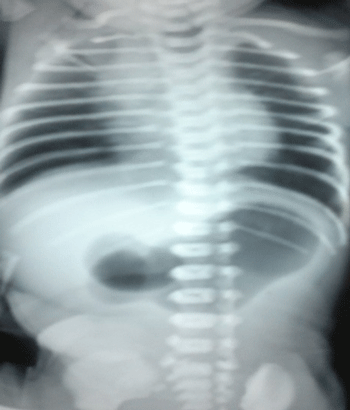

A 8-day-old boy weighing 1.9kg, born preterm at 32 weeks gestation as a normal delivery with a birth weight of 2.3kg with good Apgar score, was referred for non-bilious, non-projectile vomiting of curdled milk immediately after feeds. Examination revealed upper abdominal distension with visible peristalsis from left to right (Fig.1). An erect X ray of the abdomen (Fig. 2) showed a dilated stomach and no gas in the abdomen distal to the pylorus. An air contrast study was done which again showed a dilated stomach and no gas distally. An ultrasound abdomen showed gaseous distended stomach with a short segment thickening of pyloric wall obliterating the pyloric lumen. Following correction of electrolyte and acid base imbalance, with a diagnosis of pyloric obstruction, suspected pyloric atresia, the neonate was explored to find a congenital pyloric atresia with no gap between the two ends. Resection of the pylorus with anastomoses of the antrum of the stomach with the first part of the duodenum was done safeguarding the structures posterior to the first part of the duodenum. Broad spectrum antibiotics and total parenteral nutrition through a central line were the mainstay of post-operative management. The post-operative recovery was thus uneventful and the baby was discharged on 12th post-operative day on full breast feeds.

Figure 2: Dilated body and antrum of the stomach with no gas in the distal bowel loops.